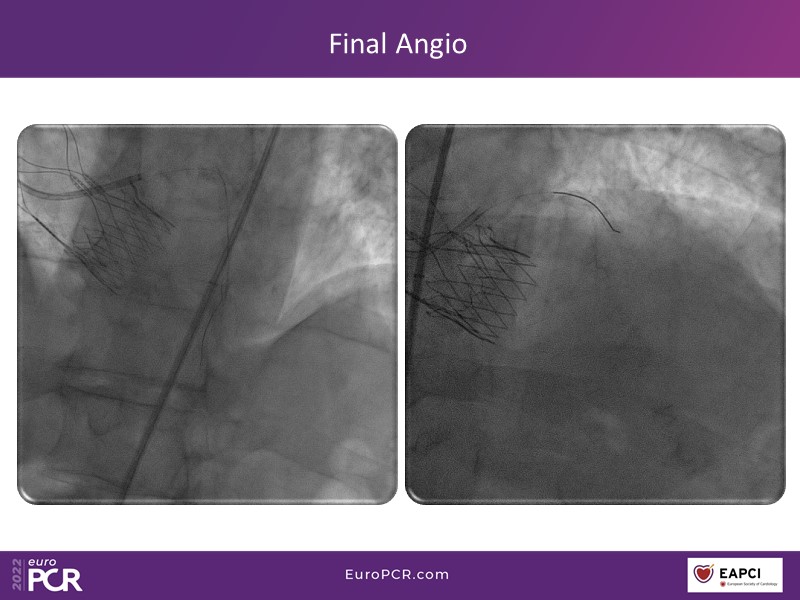

Alexandre Abizaid, Marco Valgimigli, Fazila Malik, Luca Testa, Patrick W. Serruys, Damiano Regazzoli, Kumar Prathap, and Sandeep Basavarajaiah take turns in this session to discuss two innovative technologies: a stent platform with nanotechnology and a novel drug-coated balloon (DCB). These novel technologies both have unique features that could change daily practice and improve outcomes.

- To find out more about the application and mechanism of a sirolimus coated balloon for coronary artery disease treatment with case presentations in complex settings

- To look at the technology behind the products, what the key data suggest and important takeaways from case permutations